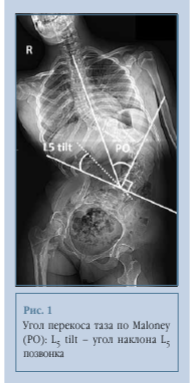

В исследование вошли 45 пациентов 10-17 лет, проходивших лечение в 2012-2024 гг. Всем пациентам выполнены постуральные рентгенограммы (в положении сидя). Величину деформации позвоночника оценивали по методике Cobb до и после операции. Также оценивали параметры сагиттального и фронтального баланса, в том числе во фронтальной плоскости - перекос таза по методике Maloney, наибольшая надежность данного метода показана Shrader et al. [16]. Изучили показатель наклона L5 позвонка, определяемого как угол между линиями, проведенными через верхние границы подвздошных гребней и по краю верхней замыкательной пластинки L5 позвонка (рис. 1).

Возможным объяснением обнаруженной связи может являться то, что пояснично-крестцовое сочленение в норме является очень стабильным благодаря подвздошно-поясничным связкам, фиброзному кольцу и передней продольной связке [18, 20], на основании чего высказано предположение, что стабильное пояснично-крестцовое сочленение может позволить исправить перекос таза за счет коррекции положения L5 позвонка [18, 21]. Это предположение также подтверждается обнаруженной нами прямой связью между коррекцией основной деформации и коррекцией перекоса таза (рис. 1), то есть можно добиться уменьшения перекоса за счет коррекции основной деформации, о чем также сообщали Wild et al. [22] и Frischhut et al. [23]. Исходный наклон L5 позвонка более 15° может говорить о нестабильности пояснично-крестцового сочленения [10, 21], что не позволяет скорректировать положение таза путем изменения положения позвонка, в пользу чего говорит отсутствие достоверной корреляции между наклоном L5 и коррекцией наклона таза в группе III. Возможно, используя тазовую фиксацию, мы можем исправить положение таза в пространстве независимо от исходного наклона L5 позвонка. Выявленные взаимосвязи рентгенологических параметров, влияющие на коррекцию перекоса таза, представлены на рис. 12.